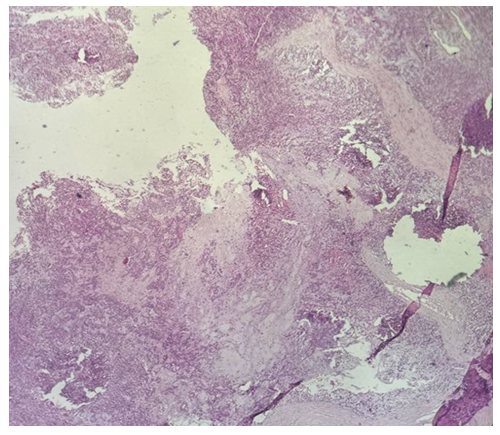

| Picture 4. Surgically resected specimens of salivary gland tumors. Histological appearance of undifferentiated carcinoma (4 cases), localized in the right palatal mucosa (Nos. 1297, 1298) and mandible (Nos. 1383, 1384). The tumor is composed of solid sheets and nests of atypical epithelial cells with a high nuclear–cytoplasmic ratio, marked nuclear pleomorphism, hyperchromasia, and absence of glandular differentiation (H&E stain) |

A total of 48 patients with salivary gland tumors were examined between 2023 and 2025. The cohort included 45 males and 3 females. The most frequent malignant neoplasms were undifferentiated carcinoma (4 cases) and adenocarcinoma, stage I (3 cases). Benign tumors included pleomorphic adenoma (1 case) and monomorphic adenoma (1 case).Histopathological examination revealed distinct morphological patterns characteristic of each tumor type. Representative photomicrographs are presented below. | Figure 1. Undifferentiated carcinoma (H&E stain, ×10) |

Morphological description: Tumor tissue demonstrates a solid growth pattern with sheets of atypical epithelial cells. The cells show high nuclear-cytoplasmic ratio, hyperchromatic nuclei, and loss of normal glandular architecture. Areas of necrosis and irregular stromal infiltration are evident. No clear glandular or squamous differentiation is observed, which corresponds to the diagnosis of undifferentiated carcinoma. Figure 1. Histological section of undifferentiated carcinoma of the salivary gland showing solid sheets of atypical cells with hyperchromatic nuclei and absence of glandular differentiation (H&E stain, ×10). | Figure 2. Undifferentiated carcinoma (mandibular localization, H&E stain, ×10) |